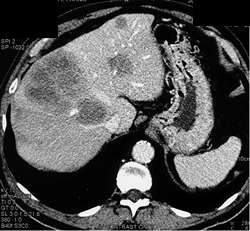

Focal Nodular Hyperplasia (FNH)